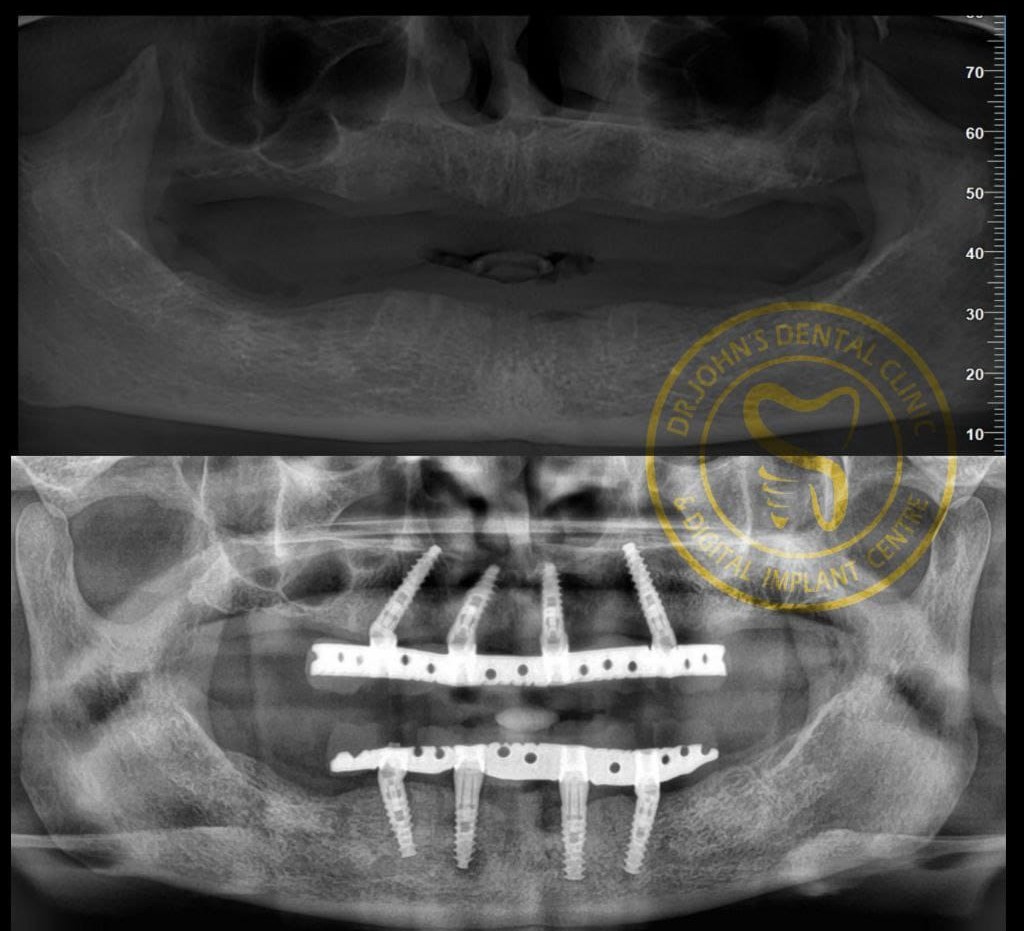

Expertise in Full Mouth Implants (All-on-4/6), Zygoma & Pterygoid implants, and Implant-supported prostheses.

Expertise in Full Mouth Implants (All-on-4/6), Zygoma & Pterygoid implants, and Implant-supported prostheses.

Advanced implantology allows same-day teeth replacement or full-arch rehabilitation using the All-on-4 technique, providing quick and effective results.